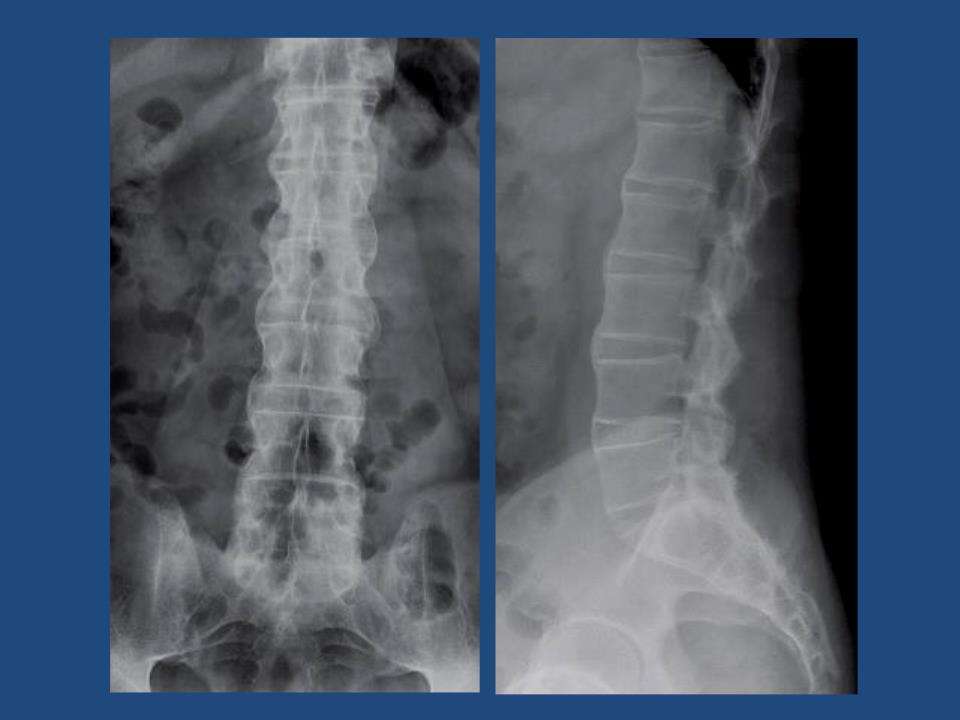

• 强直性脊柱炎患者应怎样通过日常劳动进行锻炼

强直性脊柱炎是指骶髂关节以及脊柱附着点位置的炎症,和HLA- ...

• 成都强直医院医生介绍:强直性脊柱炎的早期症状有哪些?

脊柱炎作为一种常见的脊柱疾病,对于人们的身体和生活都会造 ...

强直性脊柱炎这个疾病的特点就是侵犯骶髂关节、脊柱为主,然 ...

强直性脊柱炎是人们的骶髂关节以及脊柱的部位出现炎症的一种 ...